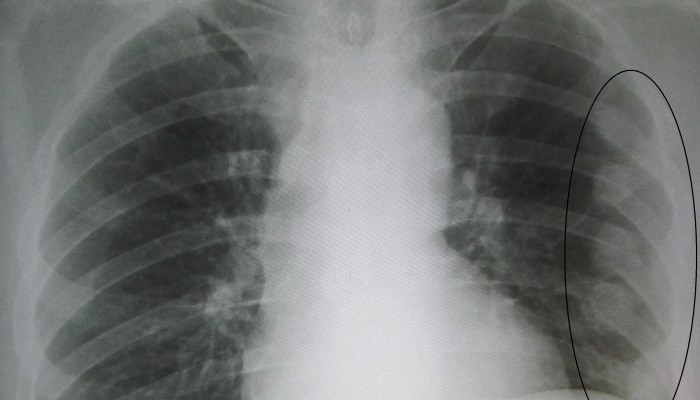

Прежде чем приступать к лечению пострадавшего, нужно точно определить причины его недомогания. Симптомы перелома ребер являются довольно специфическими, поэтому поставить диагноз достаточно просто. Проблемы с этим могут возникнуть, если пациент находится в бессознательном состоянии, а также при возникновении различных осложнений. Обычно, у специалистов не возникает вопроса, как определить перелом ребра. Для диагностики могут быть использованы следующие методы:

- Рентгенография грудной области. Этот способ диагностики позволяет не только подтвердить заключение врача, но и определить наличие признаков осложнений.